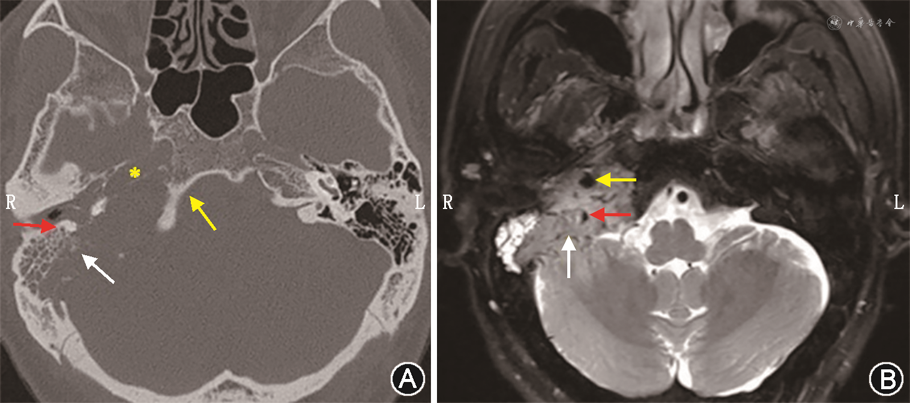

常规的辅助检查包括听力测试、颞骨高分辨CT、MRI、磁共振血管成像(magnetic resonance angiography,MRA)和磁共振静脉成像(magnetic resonance venography,MRV)、数字减影血管造影(digital subtraction angiography,DSA)、血生化检查等。依据病变侵犯结构和程度的不同,听力下降可表现为传导性听力损失、感音神经性听力损失或混合性听力损失等。影像学检查对肿瘤的定位,定性非常重要。颞骨高分辨CT扫描,可显示颈静脉孔扩大、周围骨质边缘呈现不规则蚕蚀样改变。应特别关注肿瘤累及面神经骨管、颈内动脉骨管、舌下神经管的程度(图2A);副神经节瘤具有极其丰富的血管结构,高流速血管在MRI上表现为流空低信号,慢流速血管表现为高信号、斑点,再加上肿瘤实质信号,形成所谓的“胡椒盐”征(图2B),是其特征性表现;增强MRI应特别关注肿瘤与颈内动脉、椎动脉的关系,对于向前方生长的肿瘤,颈内动脉可能被推压或包绕。另外,大多数颈静脉孔区副神经节瘤可侵入颈静脉球内,并沿乙状窦向上生长,向下沿颈内静脉生长。了解肿瘤在乙状窦及颈内静脉中的位置,有助于术者确定乙状窦填塞位置及颈内静脉结扎部位。颈静脉孔区副神经节瘤与颈静脉球、颈内动脉关系密切,建议常规行磁共振无对比剂血管成像技术(MRA、MRV)检查。MRA可以评估肿瘤血液供应及其附近的动脉分布,颈内动脉可能被包绕,被肿瘤组织压迫狭窄;MRV可以明确乙状窦、颈静脉球、颈内静脉是否通畅或被阻塞,以及对侧乙状窦、颈静脉球、颈内静脉是否优势引流。一旦优势侧乙状窦、颈静脉球、颈内静脉被阻断,对侧侧支循环开放不足可导致静脉相关性颅内高压。DSA可了解肿瘤血供,评估异常血管团的范围、供血动脉、回流静脉等信息,清晰显示血管变异情况,并能动态显示病灶血流动力。颈内动脉球囊闭塞实验可以评估动脉被阻断后脑组织的耐受性,判断患者是否可以耐受动脉闭塞治疗,明确颈内动脉损伤后结扎的可行性。术前可行供血动脉栓塞,以减少术中出血。